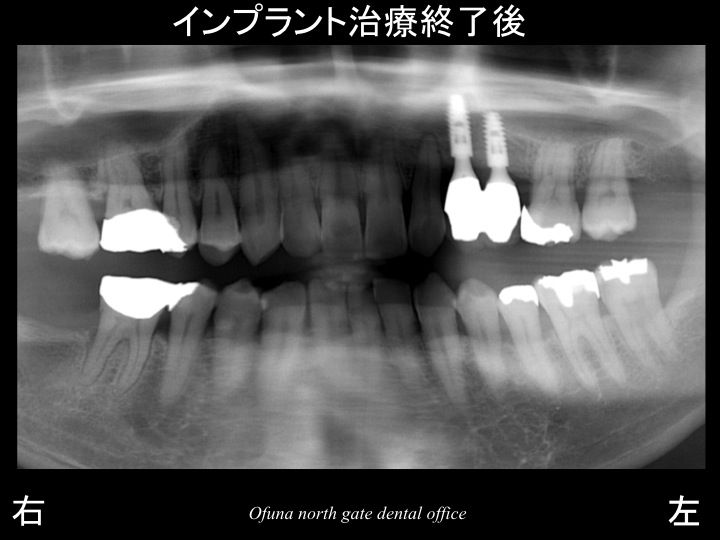

以下は、インプラント治療後です。

使用したインプラントは、アンキロス インプラント

です。